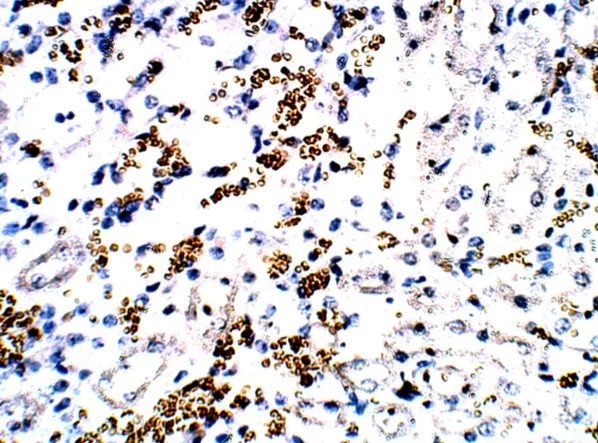

Immunohistochemistry (Formalin/PFA-fixed paraffin-embedded sections) - Anti-FOXP3 antibody (AB75763)

Immunofluorescence of tumors from mice treated with MN-siPDL1 and gemcitabine. There was evidence of an increase in cell-mediated cytotoxicity, as evidenced by a decrease in the infiltration by immunosuppressive Foxp3 + regulatory T (Treg) cells detected using ab75763.

This image has been cropped from the origanal figure.

This image is taken from Fig 5. Byunghee Y. et al. RNAi-Mediated PD-L1 Inhibition for Pancreatic Cancer Immunotherapy, Sci Rep. 2019; 9: 4712. doi: 10.1038/s41598-019-41251-9. http://creativecommons.org/licenses/by/4.0/.